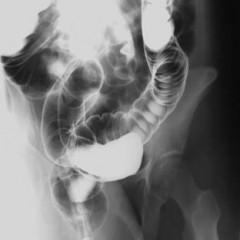

На нормальной рентгенограмме толстой кишки с двойным контрастированием форма и размеры органа остаются неизменными, не наблюдаются сужения или расширения просвета, а контрастное вещество равномерно распределено по стенкам. Складчатость слизистой оболочки соответствует норме.

После подготовки выполняется обзорная рентгенография органов брюшной полости. Затем в кишечник с помощью клизмы вводится контрастное вещество, и, меняя положение пациента (на боку, на животе, на спине, стоя), делают несколько дополнительных снимков. Последний снимок делается после опорожнения кишечника. При двойном контрастировании на заключительном этапе кишечник наполняется воздухом для получения изображений его внутренней поверхности.

После подготовки проводится обзорная рентгенография органов брюшной полости. Затем в кишечник вводится контрастное вещество с помощью клизмы, и выполняются дополнительные снимки в разных положениях пациента (на боку, на животе, на спине, стоя). Последний снимок делают после опорожнения кишечника. При двойном контрастировании на заключительном этапе кишечник наполняется воздухом для получения изображений рельефной внутренней поверхности.

наличие дефектов наполнения (мелкие опухоли в кишечнике; злокачественная опухоль, приводящая к сужению просвета восходящей ободочной кишки);

дефекты заполнения (указывает на выпячивания и углубления в стенках органа, куда проникает контрастное вещество; множественные дивертикулы);